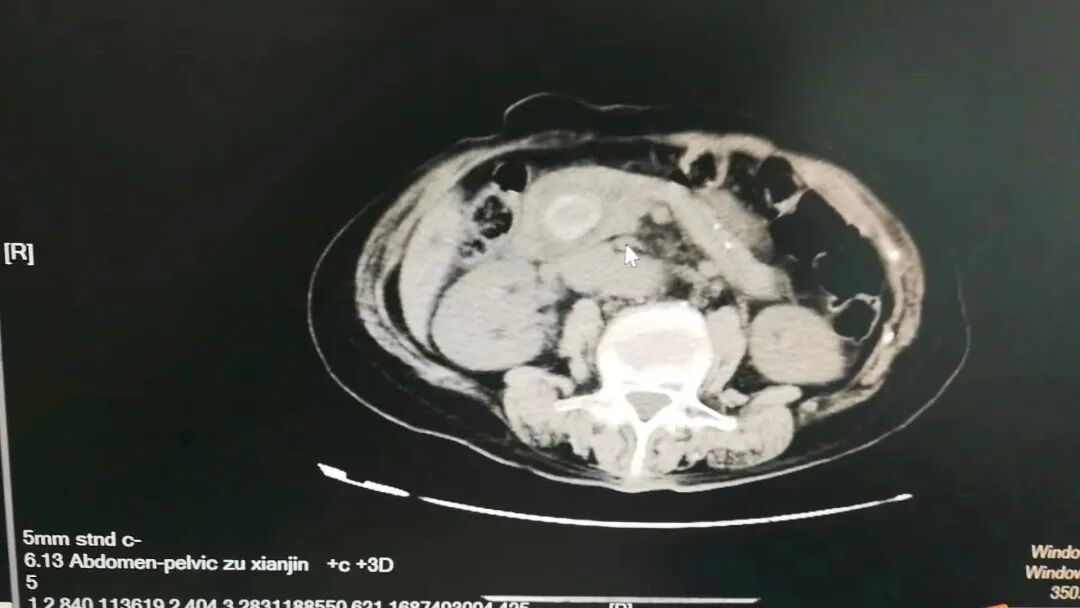

入院后予以抗感染、解痉止痛等对症治疗后,章阿姨病情无明显好转,仍然反复腹痛,疼痛剧烈时在床上直打滚!完善增强CT等相关检查后患者“胆总管多发结石并急性胆管炎,肝内外胆管扩张”诊断明确,手术指征明确。

▲CT影像